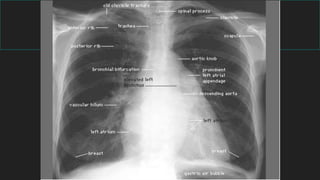

Radiología de tórax normal

4- Mediastino

BORDE DERECHO

BORDE IZQUIERDO

Rx Torax A/P

5- Hilios y vía aérea

División topográfica Frente